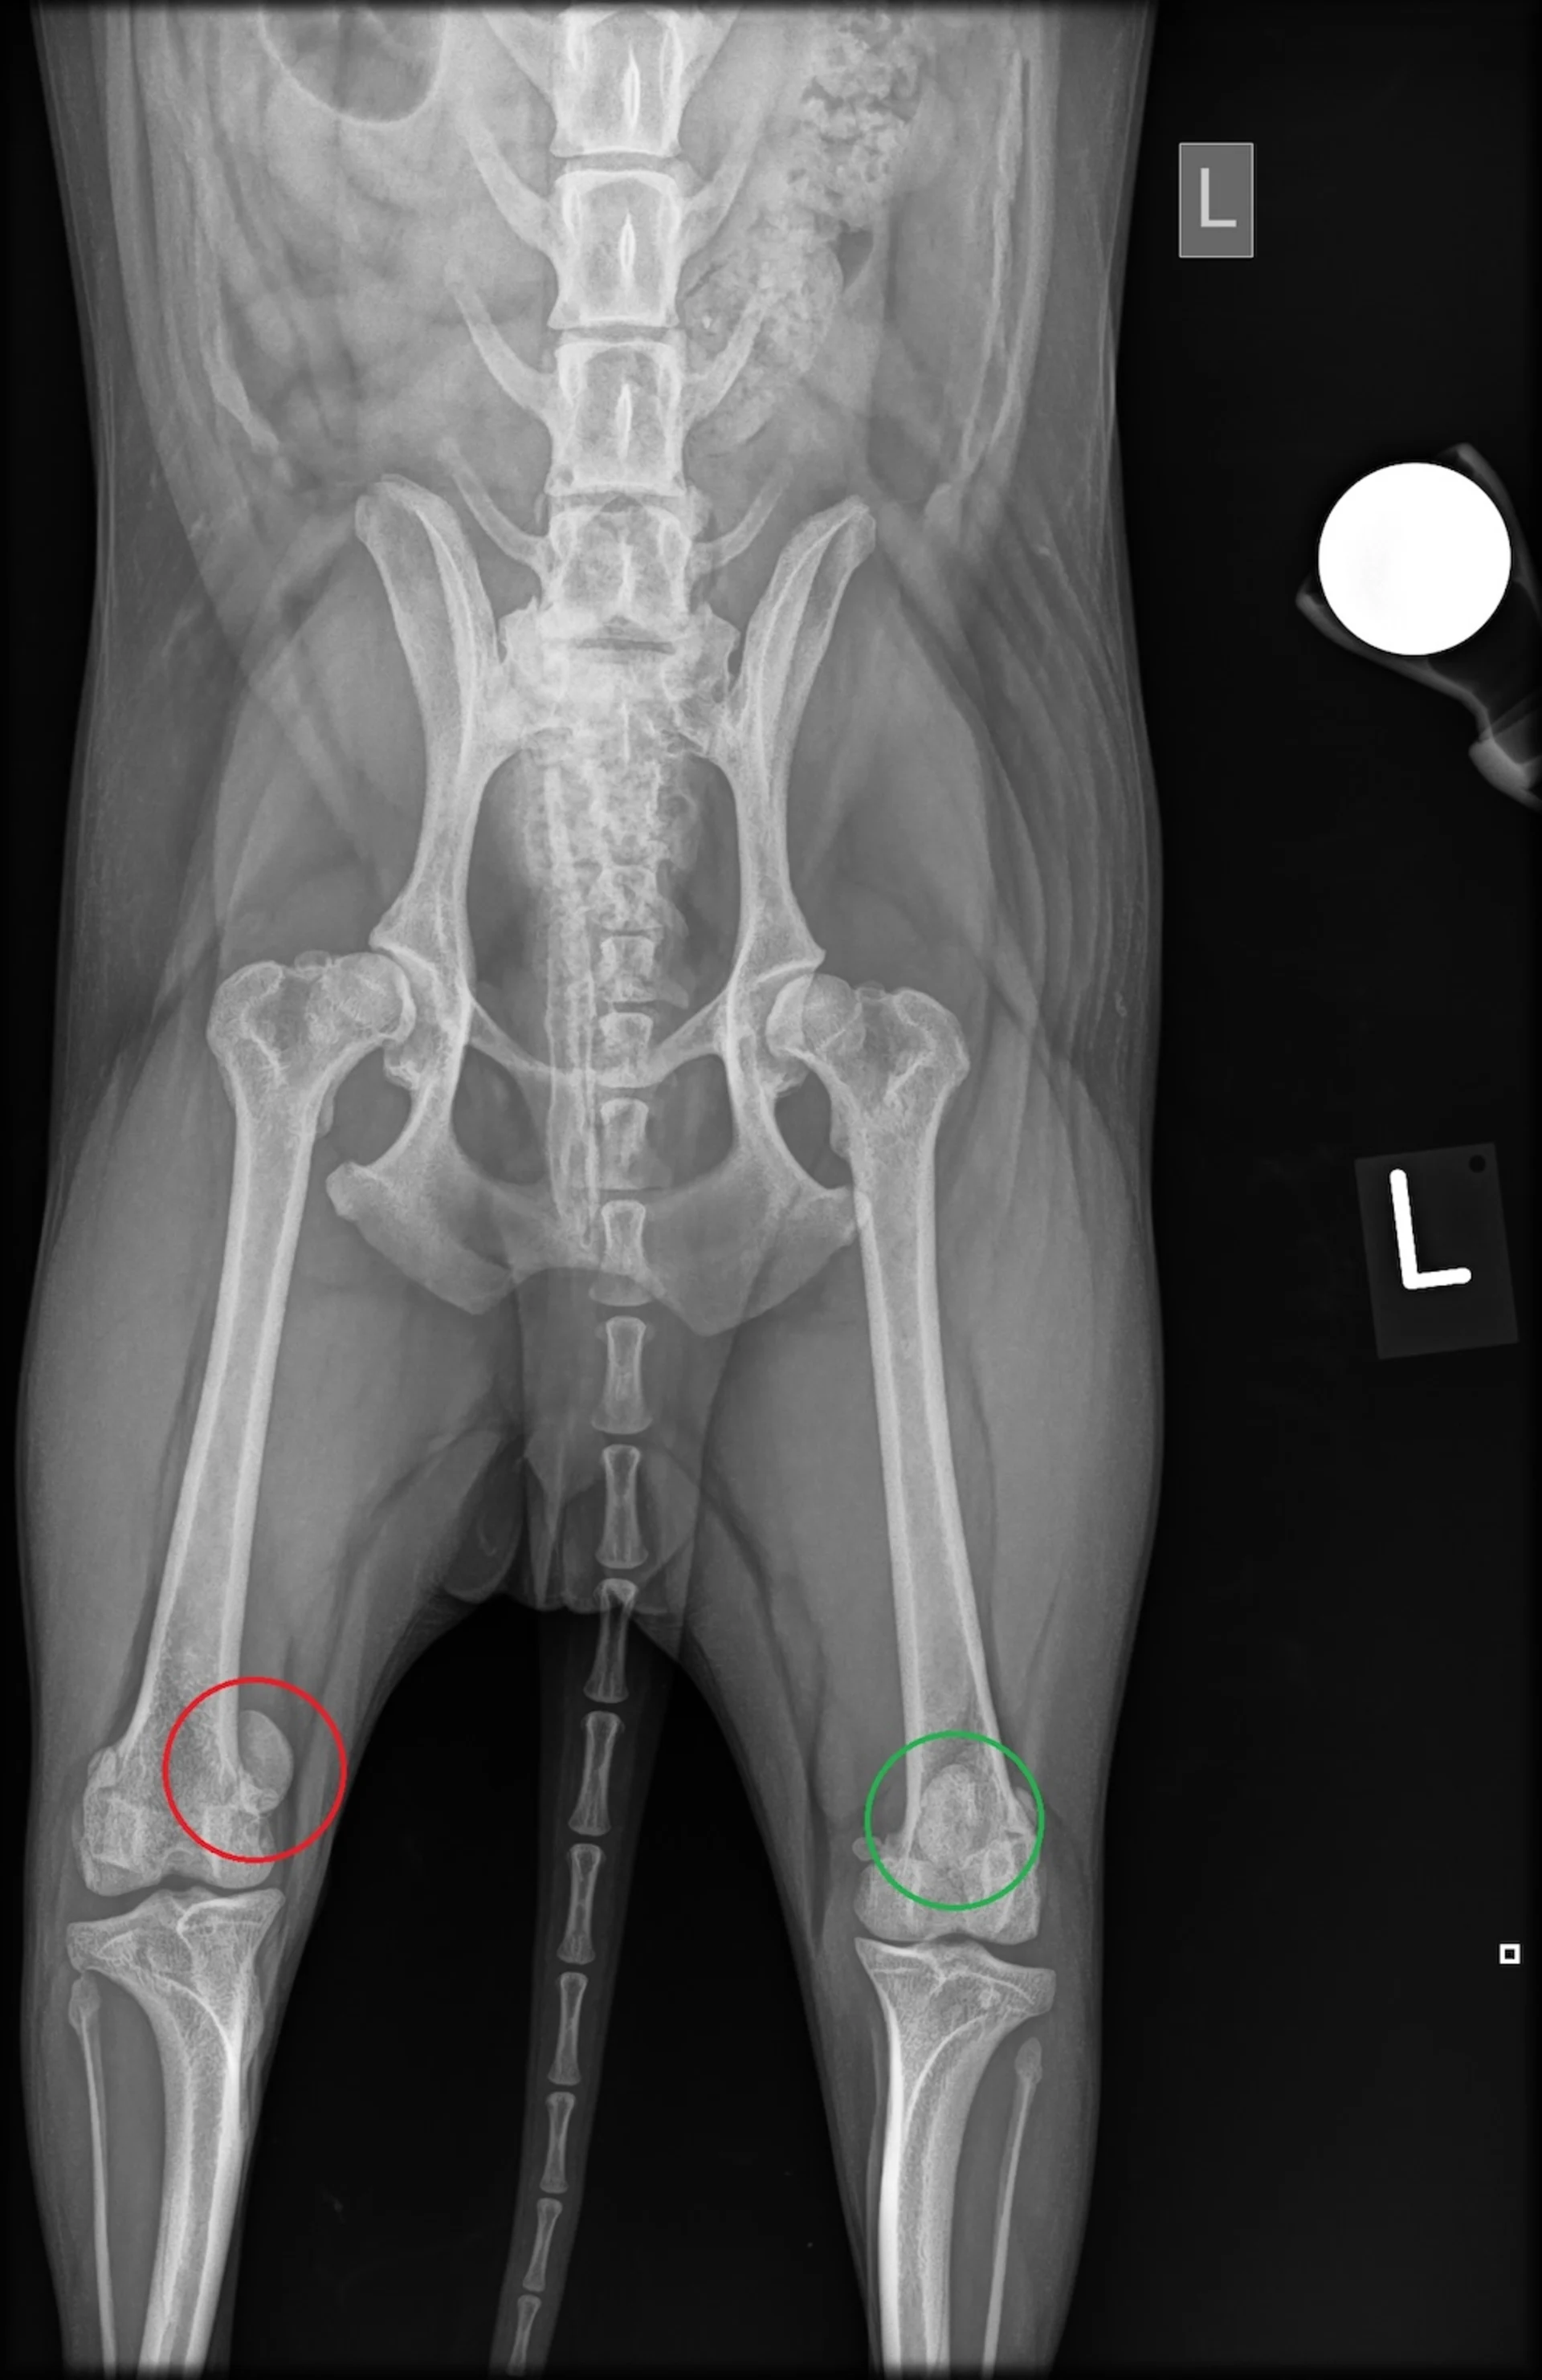

Röntgenbild